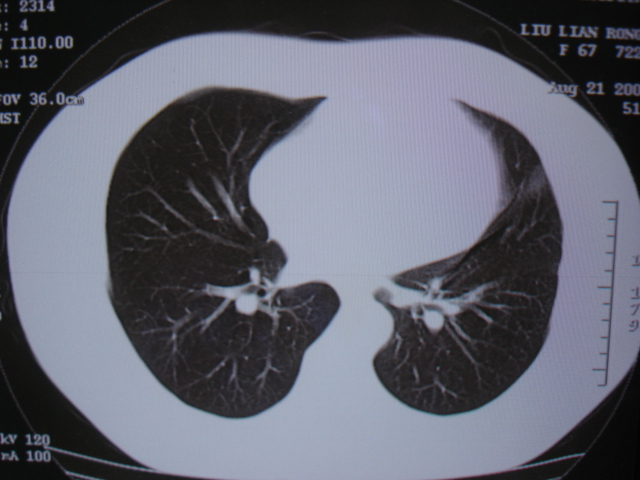

第三次ct2009.8.21

炎症,最厚一次已吸收

考虑 左肺上叶炎症感染 [炎性假瘤可能性大]。

不排除肺癌